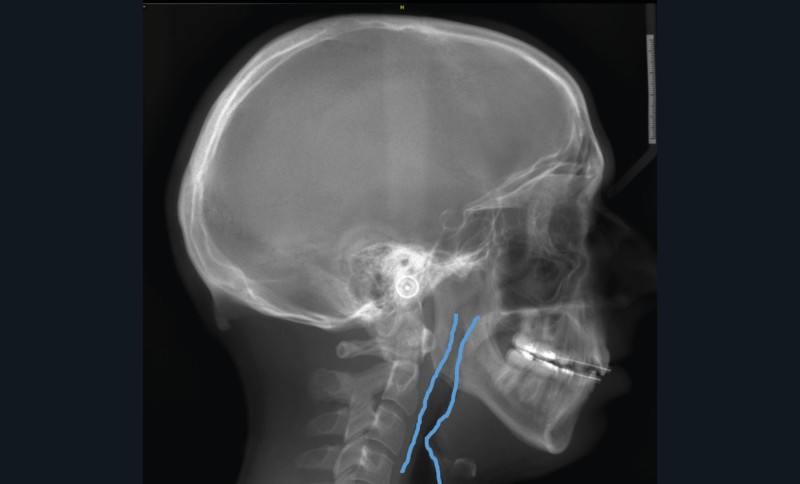

Le Pr Pierre Bouletreau nous rappellera le rôle de chacun des participants à une Réunion de concertation pluridisciplinaire (RCP) du Syndrome d’apnées hypopnées obstructives du sommeil (SAHOS) et insistera sur les dernières indications et contre-indications des orthèses d’avancée mandibulaire et de la chirurgie d’avancée maxillo-mandibulaire (fig. 14a-b).